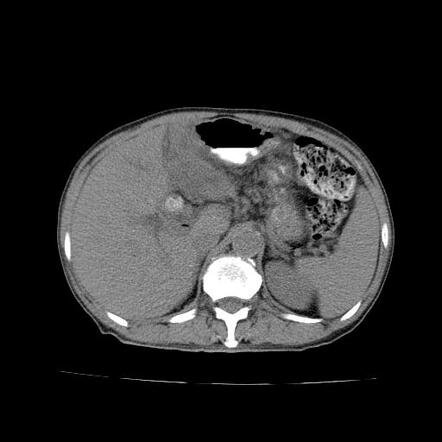

How We Diagnose?

Provide detailed views of the bile ducts, liver, and surrounding organs to detect blockages and tumor spread.